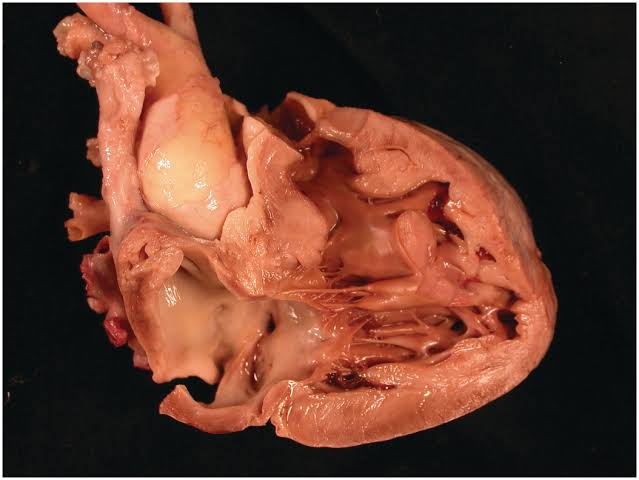

This is a warning sign that your heart is gradually failing and you need to attend to it.

If your heart stops working, it means you die immediately.

So you need to treat that heart condition today.

Chest pain means there is something wrong with your heart.

You need to treat it immediately before it becomes worse and put you in more danger.

Cadix capsule will go into your body, go to your heart and lungs and start fixing the issues.